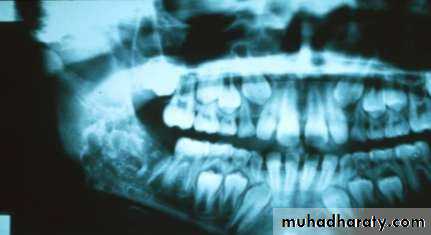

• Compound Complex

• The compound type shows apparent tooth shapes while the complex type appears as uniform opaque mass with no apparent tooth shapes present• Copyright 2003, Elsevier Science (USA). All rights reserved.